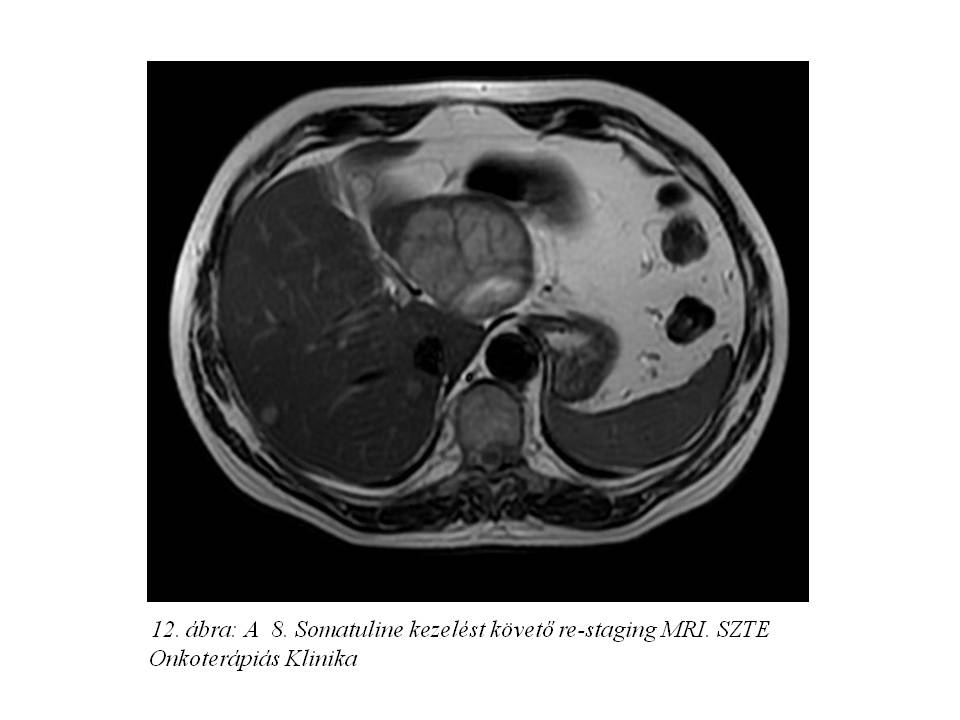

Ezt követően bőrgyógyászati ellátás vált szükségessé testszerte jelentkező viszkető urticaria miatt, felmerült octreotidra való túlérzékenység lehetősége. Emiatt kezelését a továbbiakban lanreotiddal (Somatuline) folytattuk, ugyancsak 4 ciklusonként végzett re-staging mellett. Jelenleg a hasi MR vizsgálaton (11. ábra, 12. ábra, 13. ábra) változatlan status látható, a chromogranin szint emelkedése mellett (266,9 – 310 – 427 ng/ml).